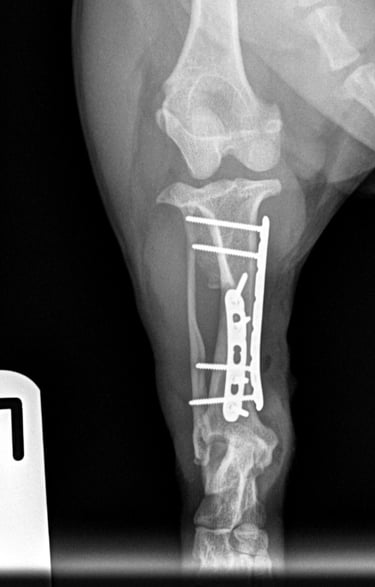

The fracture site was identified and anatomically reduced using bone-holding forceps. Internal fixation was achieved using dual plating in an orthogonal configuration, providing optimal mechanical stability.

Medial plate: A 1.5 mm 7-hole locking compression plate (LCP) was applied in bridging fashion, secured with two bicortical locking screws in both the proximal and distal fracture fragments.

Cranial plate: A 1.5 mm 5-hole LCP was also applied in bridging mode, with two locking screws in the proximal fragment (the most proximal bicortical and the distal monocortical due to proximity to the fracture line), and two bicortical locking screws in the distal fragment.

Postoperative radiographs confirmed excellent implant positioning, appropriate fracture alignment, and good apposition of fracture ends (Fig. 3 and 4).

Fig. 3